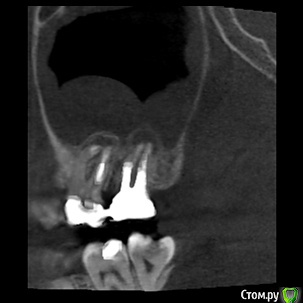

Tymchynskyi Опубликовано 2 мая, 2016 Поделиться Опубликовано 2 мая, 2016 (изменено) Пациентка обратилась по поводу периодически повторяющихся ноющих болей в области 17го зуба, постоянное ощущение дискомфорта.Месяц назад пошла на консультацию к ЛОРу где ей поставили диагноз правостороннего гайморита.Сначала баловались *кукушками* - не помогло, затем сделали прокол, и со слов пациентки, док. сказал что из пазухи исходил кариозный запах, характерный для проблемного зуба.Объективно: 16-17 зубы лечены 2г назад и покрыты МК спаянными коронками.Десневой край вокруг коронок цианотичный, нарушена БШ.В 17 зубе 3-ногая ВКВ, в 16 СВШ.Вертикальная перкуссия 17 слабо болезненная.Отправил на КТ.На буккальных апексах 16-17 и небном 17 очаги деструкции.Но больше всего интересует наличие инородного тела над апексом небного корня зуба 17(диаметр порядка 2мм).Или это артефакт??То ли обтурационный материал мигрировал вглубь пазухи, то ли ЛОР чето намудрил при вмешательстве...Что скажете?Какие прогнозы? Изменено 2 мая, 2016 пользователем Tymchynskyi Ссылка на комментарий

Л Ю С Я Опубликовано 3 мая, 2016 Поделиться Опубликовано 3 мая, 2016 + динамическое наблюдение 6,12 , 24 месяцев. Не торопитесь из пазухи инородное тело вынимать. Лучше подумайте как извлечь вкладку и свш без вреда для твёрдых тканей. И имеет ли смысл. Оцените количество оставшихся тв тканей после снятия коронки Ссылка на комментарий

ger_berra Опубликовано 5 мая, 2016 Поделиться Опубликовано 5 мая, 2016 У пациентки зуб 2.6 был запломбирован цинкоксид-эвгеноловой пастой, в каналах и на снимке было плотно (снимков, к сожалению, показать не смогу - пациентка не моя). Но был выведен материал у небного корня размером 2Х1,5 мм. Обострения гайморита периодические, с проколами, госпитализацией и т.д. Если очень сильно придираться, то слегка была расширена периодонтальная щель. Зуб перелечили, горячая гуттаперча. Улучшений нет. Гайморотомия, грибы в пазухе, тяжелая операция с трудной реабилитацией, но только после гайморотомии ничего не беспокоит. Вот из-за такой маленькой капли материала пациентка на полгода выпала из жизни (((Ухххх! Если это точно грибы,то даже с ретритом не парьтесь.Хотя на Ваших нарезках признаков грибов нет.Грибы поселяются рядом с " пломбиром" (с) Грибы выглядят ,как творог с вкраплениями ( это мицелий гриба). Если по типу "пены",то это начальная грибковая инфекция. Прредставьте,извлекли вкладку,ретритмент на высшем уровне,а от зуба остался пень без феррула( учитывая квалификацию ортопеда,сделавшему спаянные коронки!) бесплатно хотите работать? Мотивируйте на удаление и имплантацию. И спите спокойно. Ссылка на комментарий